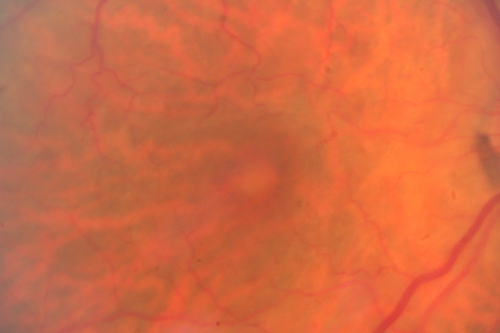

Vitreomacular Traction 1 month - 20/60 vision - Fellow Eye Normal - 80 Year Old Man

80-year-old man has a macular pucker in the right eye with vitreomacular traction and vision loss for 1 month.  His vision seems about stable to him.   OD 20/60.

(these images are from initial presentation)